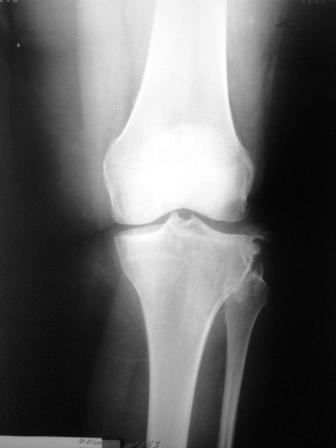

Сегодня на приеме была больная 27 лет, вес 120кг. Травма 7 лет назад -

ДТП. Была ЧМТ, двухсторонний перелом пилона, обширные рваные раны

бедер, голеней. Судя по нынешней картине - вывих голени слева. Ходит

практически не хромая, жалобы на неустойчивость голени при ходьбе. При

стресс тестах - грубейшая несостоятельность связочного аппарата

коленного сустава. Хотелось бы услышать мнение о целесообразности

пластического восстановления связок после столь длительного периода

нестабильности сустава.

Имя     : SDC10833.JPG